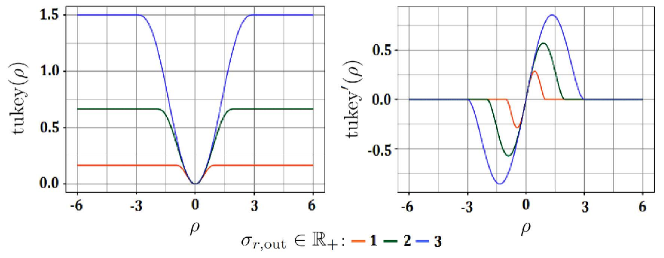

with being a tuning parameter controlling the outlier detection/removal of these functions [Beaton 1974]. As shown in Figure 5, the parameter defined the range of inputs over which the Tukey’s function/derivative got saturated/vanished. This way, the outliers manifested by large residuals or gradients could be suppressed. The minimum and the maximum of occurred at and , respectively.

Since the neighborhood graph was undirected, we only considered nonnegative residuals as the domain of the Tukey’s function and derived each weight as

| (14) | ||||

The proposed edge weights given by (14) underpinned an implicit boundary detection capability for the spatial feature-based subgraph . In addition, they enhanced the regularity or homogeneity of the subgraph by preventing any weight from being vanished. This was due to the saturation of the Tukey’s function at large features differences (gradients). These weights and the weights given by (2) for the aspatial prior-based subgraph formed the combinatorial Dirichlet integral given by (4) for the graph . Then, the classification posterior estimated for each sample (vertex) with regard to each class should fulfill (7) on the graph . The optimum posteriors of the validation/test samples of each resolution were the solutions of the system of sparse linear equations in (9).